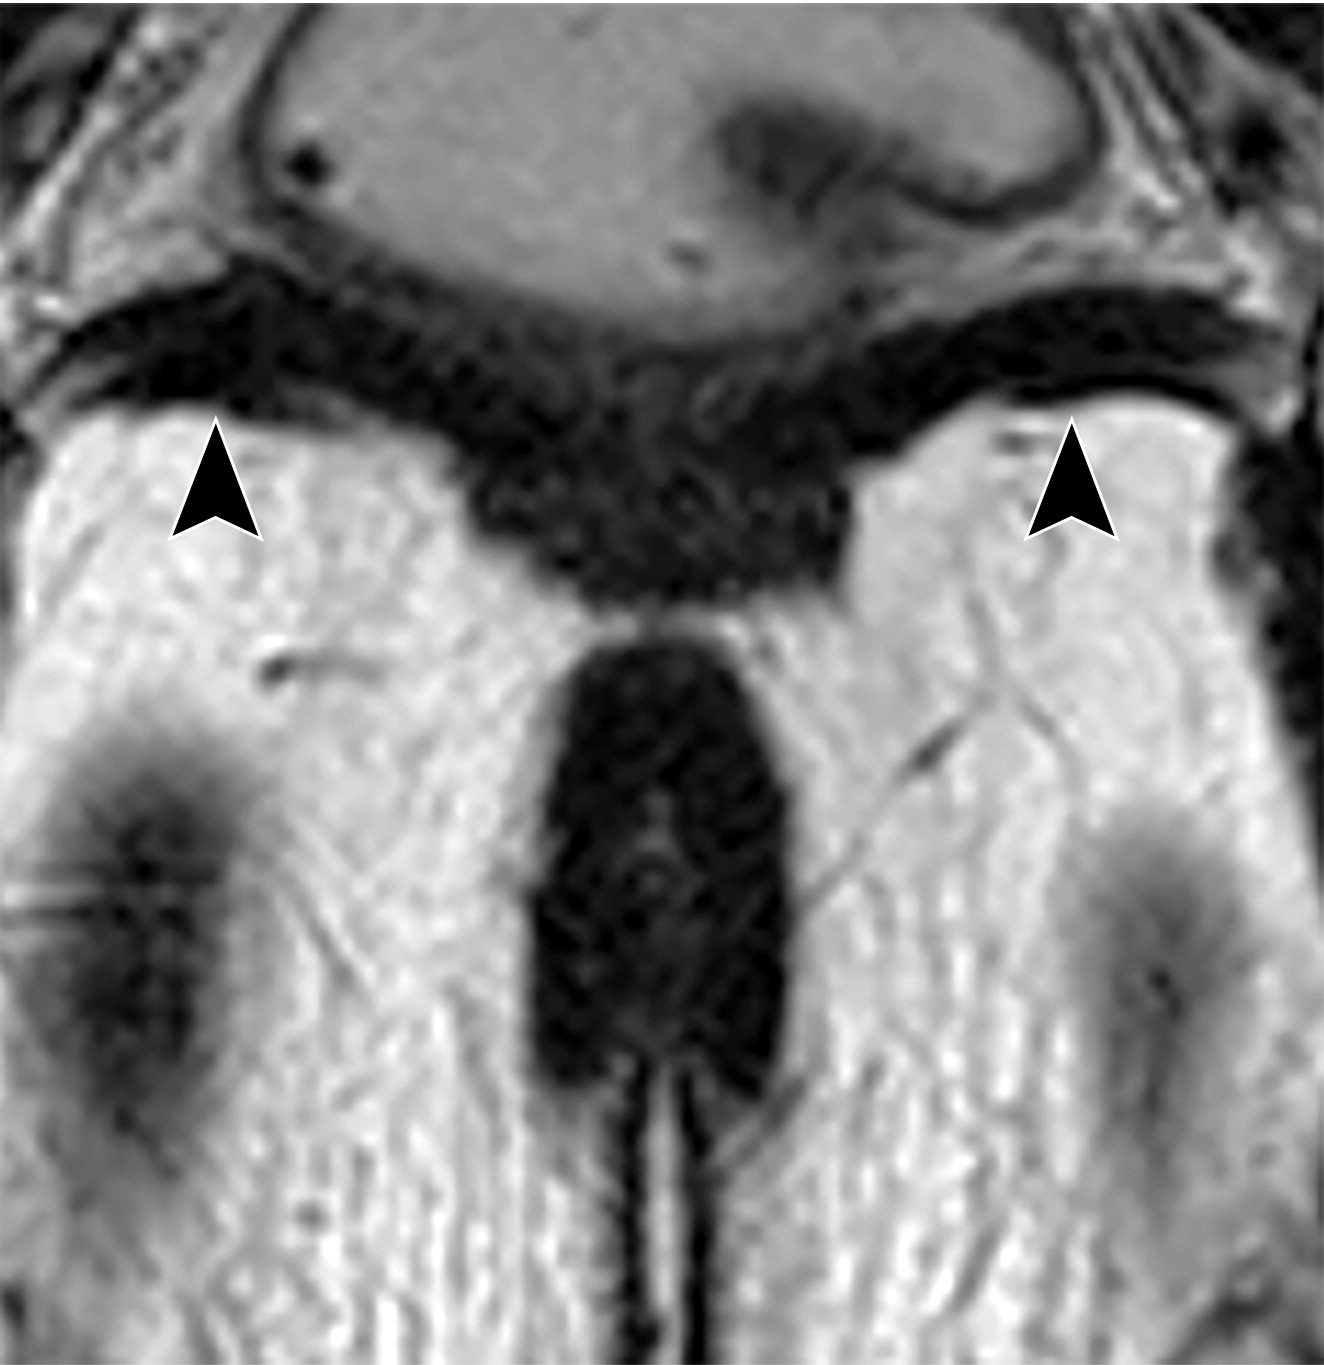

50岁以上男性骨盆和盆底的MRI解剖。

提肛肌(LA),由耻骨直肠肌(PR)、耻骨尾骨肌(PC)和髂尾骨肌(IC)组成;尾骨肌(C),前列腺(P),闭孔内肌(OI),会阴浅横肌(STP),球海绵体肌 (B), 坐骨海绵体肌(ISC),肛门外括约肌(EAS),肛门内括约肌(IAS),直肠(R),尿道括约肌(SU),也称为尿道外括约肌(U),它包围着整个膜性尿道。6774449af17bb1b8df6e83ab4e9fa158.jpeg

(上图)70岁男性,轴位T2WI示右侧会阴横肌的瘢痕及增厚(上图黑色短箭头),左侧会阴横肌相对萎缩(上图黑色长箭头)。

(下图)40岁无症状男性,轴位T2WI示正常的解剖结构(下图弯曲黑色箭头)。